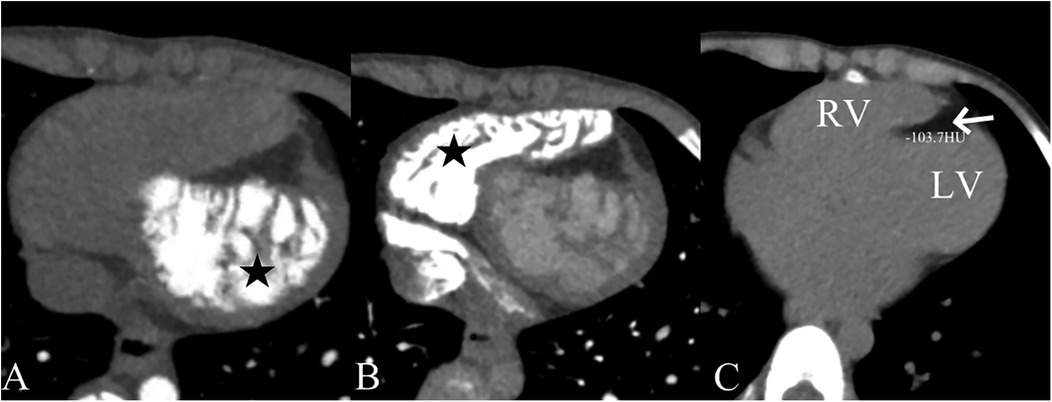

A 5-year-old boy presented with a history of cough and two fever episodes within 3 weeks. Upon admission, his vital signs were stable (T: 36.5 ℃, HR 98 bpm, RR 20 bpm). A physical examination showed the absence of wheezing, with notable cardiothoracic findings. These findings included precordial prominence, cardiomegaly on percussion (documented as 0.5-cm lateral displacement of the apical impulse from the left midclavicular line at the 5th intercostal space), and a regular cardiac rhythm without audible murmurs. His personal history (including prenatal examinations) and familial medical histories were noncontributory. A chest x-ray showed an enlarged cardiac shadow and pneumonia. Electrocardiographic findings included abnormal Q-waves, with visible Q-waves in leads II, III, aVF, and V2–V4. Additionally, ST segment changes were observed (ST segment elevation of 0.1–0.2 mV in leads V1–V4) (Figure 1A), along with QTc prolongation, left atrial heterogeneity, and double-compartment hypertrophy. Echocardiography indicated left cardiac enlargement [Left atrial volume = 28.3 ml (Z score = 4.0), LVend-diastolic diameter = 42 mm (Z score = 5.6)], a ventricular septal aneurysm in the basal and intermediate segments measuring 30 mm × 13.8 mm × 19.0 mm (Figure 2), and biventricular myocardial non-compaction with decreased LV dysfunction [ejection fraction (EF) = 40%, average E/e' = 15.4]. Computed tomographic angiography was systematically conducted for an accurate morphological assessment of the ventricular aneurysm (including topographic localization, volumetric measurement, and perianeurysmal anatomy). This technique showed left cardiac enlargement, increased trabeculation in both ventricles with a grid-like pattern, and fat density shadows within the ventricular septal myocardium (Figure 3), and a ventricular septal aneurysm. A Holter electrocardiogram showed an accelerated atrial escape rhythm (Figure 1B). Magnetic resonance imaging showed left cardiac enlargement [Left atrial volume = 34.82 ml (Z score = 4.9), LV end-diastolic volume = 76.41 ml (Z score = 4.1)], local aneurysm formation in the ventricular septum, biventricular myocardial non-compaction, and fatty infiltration in the middle and apical regions of the LV septum (Figure 4). LV systolic function was impaired (LV ejection fraction = 41.1%) and the right ventricular ejection fraction was normal (55.4%). First-pass perfusion imaging showed a perfusion defect in the ventricular septum of the mid-left ventricle and apex. Delayed enhancement imaging indicated myocardial fibrosis in the above area, which was likely secondary to myocardial ischemia.

Figure 3. Computed tomographic angiography findings showing left (A) and right (B) ventricular myocardial non-compaction (★) and fat density shadows within the ventricular septal myocardium (arrow). The computed tomographic value was −103.7 HU (C).